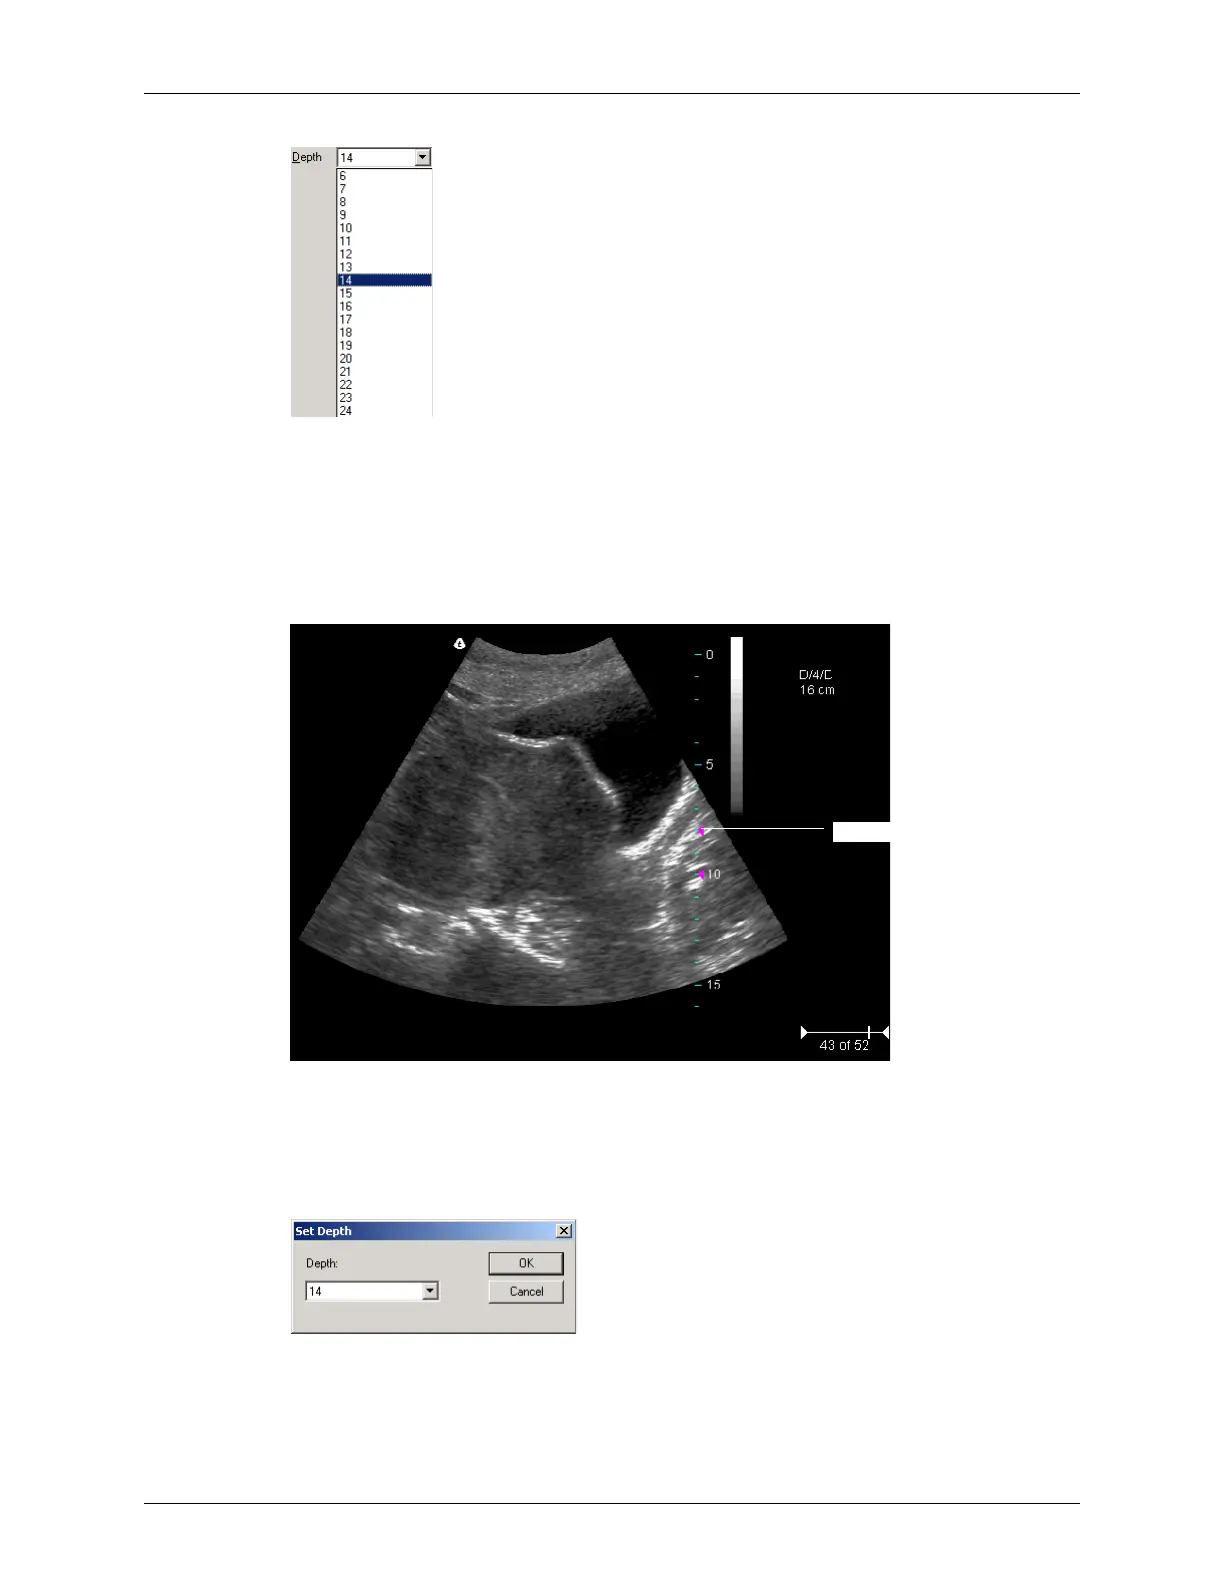

Choosing the Depth (Values in cm)

The values displayed in the menu depend on the transducer.

You can view a depth ruler on the image by selecting

View > Image Display Properties >

Depth Ruler. The figure below shows the depth ruler along the right side of the image.

Example Depth Ruler

The pink triangle on the depth ruler indicates the focus depth.

You can also use the Image menu to set the depth. To do so, complete these steps:

1. Select

Image > Depth. The Set Depth dialog box opens.

Set Depth Dialog Box

2. Select a depth value from the menu.

3. Click

OK.